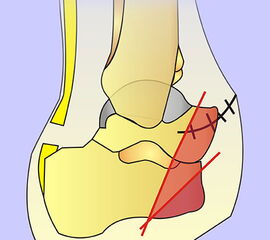

Problematik des nicht antagonisierten Sehnenzugs nach Lisfrancamputation. Die  Fußhebung ist ausgefallen. Durch Zug des M. trizeps surae resultiert eine Spitzfußstellung, die bei Neuropathie ein chronisches Ulkus im Bereich der Hauptbelastungszone hervorr

Abbildung 42

Cave!

Wird der Fußheber desinseriert, kommt es häufig zu einem Spitzfuß mit Stumpfulkus (Abb. 42). Die Prophylaxe und Behandlung bestehen in der Achillessehnendurchtrennung (entspr. Abb. 50). Eine Refixation der Fußhebersehne ist bei vorhandenem Stumpfulkus infektionsgefährdet und nicht erfolgversprechend. Besteht ein Spitzfuß über viele Monate, ist dieser regelmäßig durch eine Arthrofibrose fixiert. Dann müssen alle am Unterschenkel dorsal verlaufenden Sehnen durchtrennt, das Gelenk offen arthrolysiert und die 0-Grad-Stellung temporär mit einem K-Draht fixiert werden. Alternativ ist eine Arthrodese im oberen evtl. auch unteren Sprunggelenk möglich.